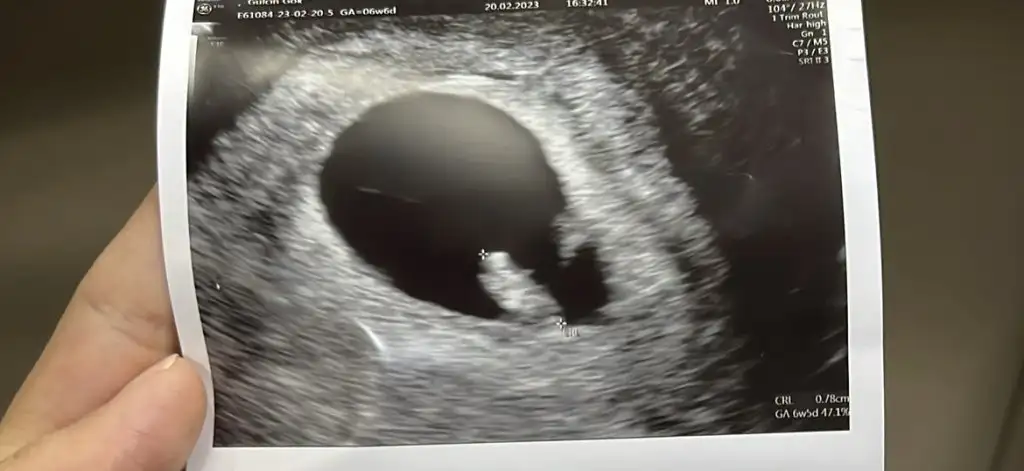

Canım çocuğum aşağıdaki gibi görünüyo şuan